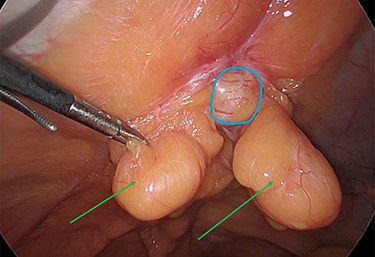

The viable omentum was reduced into the peritoneal cavity. Two lipomas were then observed attached to the parietal peritoneum (Figs 3 and 4). The lipomas were also reduced into the peritoneal cavity from within the hernia sac. Each one was 2 cm in diameter based on laparoscopic visualization using the 1 cm markings on a suction irrigation device.

Reduction of the first peritoneal lipoma (green arrow) into the peritoneal cavity.

The two peritoneal lipomas (green arrows) and the visible umbilical hernia neck (blue circle). Intracorporeal suturing of the hernia neck (green arrow) and closure of the hernial defect.